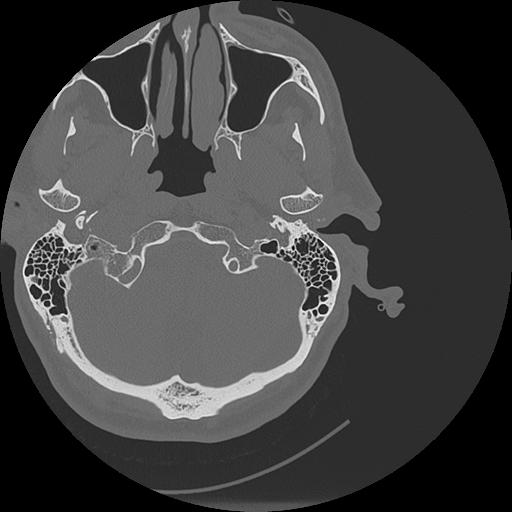

7 HUESO,,Vol,0.5,HUESO,,